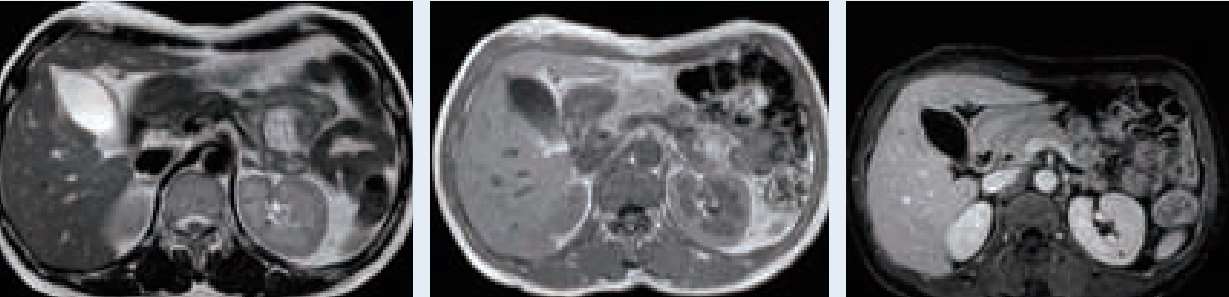

经皮经肝硬质胆道镜取石术术前磁共振检查